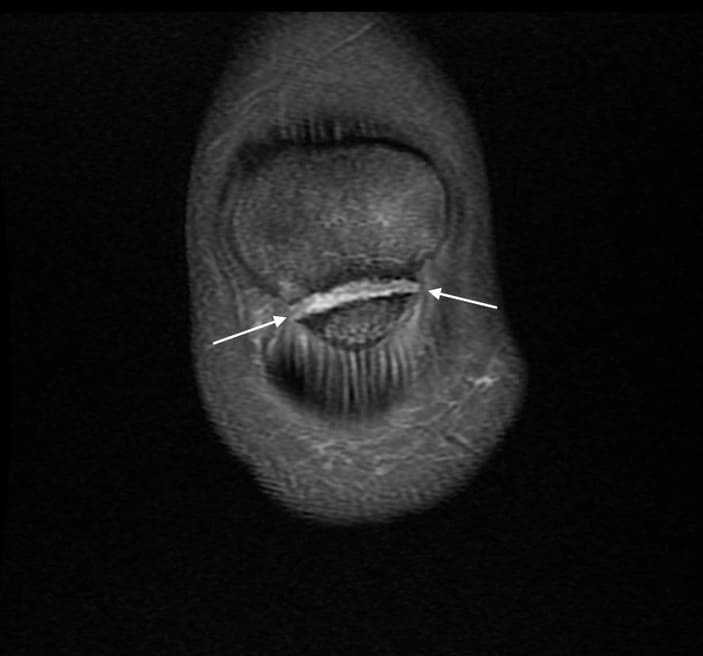

Xương bánh chè 2 mảnh

» Thông tin: Nam giới – 14 tuổi.

» Lâm sàng: Đau khớp gối.